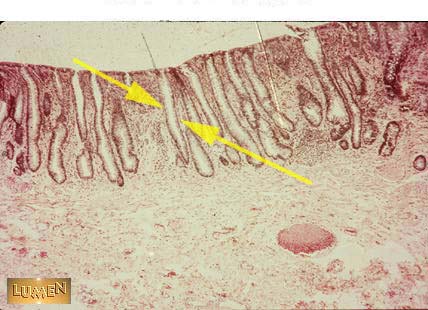

What kind of gland is this?

Simple tubular